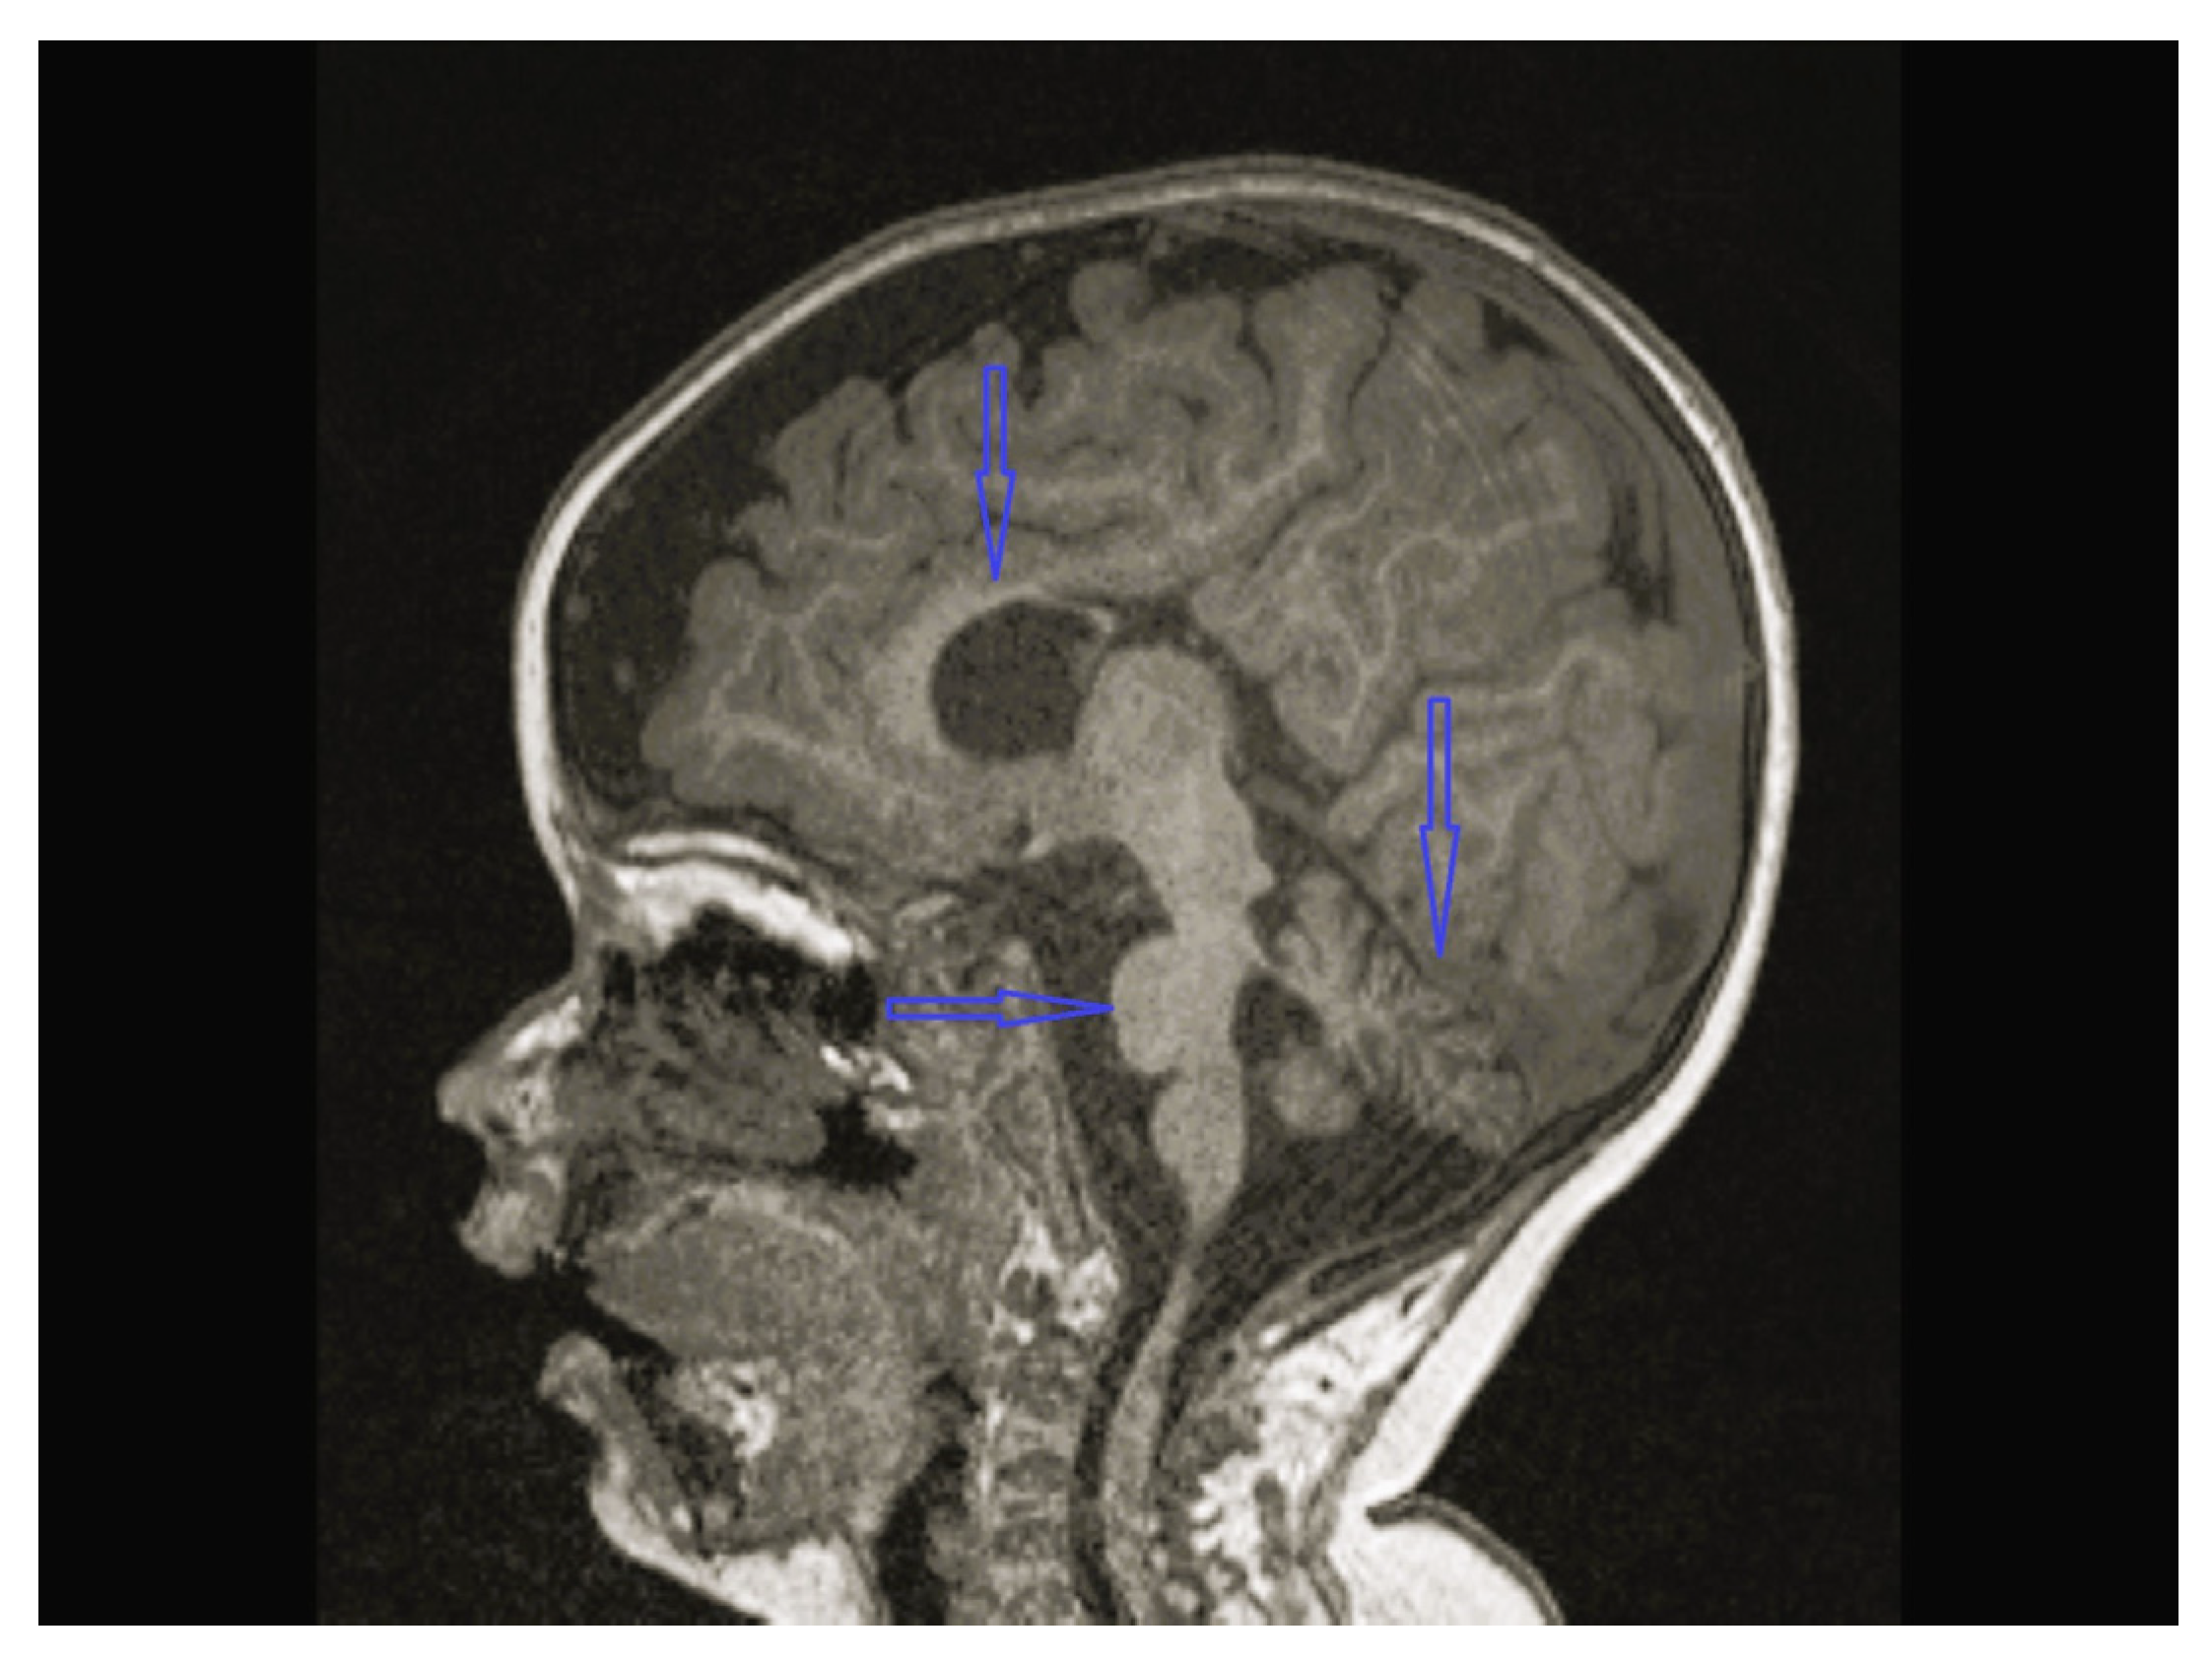

| 4 | Normal | Normal | Normal | Bilateral globus pallidus T2 hypointensity and iron accumulation | - | C19orf12c.385C>T (p.Q1239*)(p.Gln129Ter) Homozygote  | Physical therapy, carbidopa/levodopa, baclofen, |